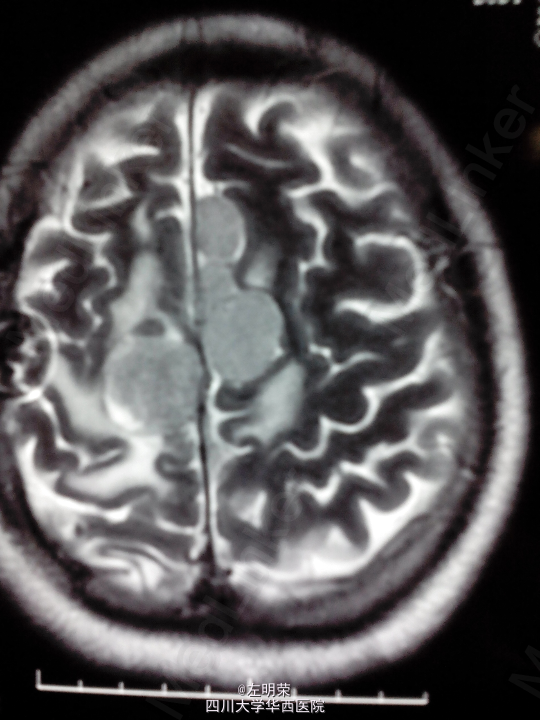

脑膜瘤术后复发(多发脑膜瘤)

左下肢乏力伴间断抽搐半年+, 患者于5年前行左侧额叶脑膜瘤切除术,术后行伽马刀治疗数次,近来出现肢体无力伴抽搐,不规律服用抗癫痫药物,昨日再发抽搐。

1、多发脑膜瘤 2、继发性癫痫